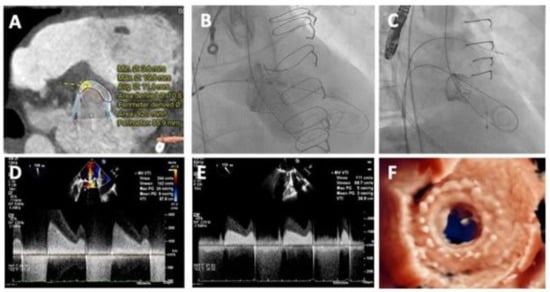

Figure 4.

Planning and performing a redo-TAVI procedure. An example of a redo-TAVI procedure where a balloon-expandable Sapien S3 Ultra (Edwards Lifesciences, USA) TAV was used to treat a degenerated self-expandable Evolut R 34 mm TAV. (A) Presence of heavy calcification located at the right cusp (green dot) and left cusp (red dot) contributed to underexpansion of the first TAV, which impacts the (B) sizing strategy of the S3. (C) A low implantation targeting node 4, was deemed safe to prevent coronary obstruction. (D–F) Fluoroscopic images demonstrating the (D) extent of regurgitation pre-procedurally, (E) targeting node 4 (white arrow) and (F) final result confirming patency of both coronary ostia (represented by stars).